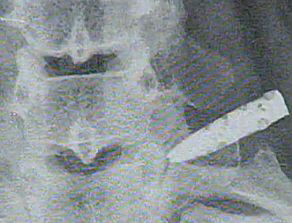

엑스레이 나타난 칼 조각은 길이가 5cm로 여성의 등뼈에 꽂혀 있었다. 그때서야 이 여성은 청소년시절에 전 애인으로부터 칼에 찔렸던 사건이 떠올랐다.

엑스레이를 통해 발견된 칼 조각은 최근 인근 병원에서 수술을 통해 제거됐다.